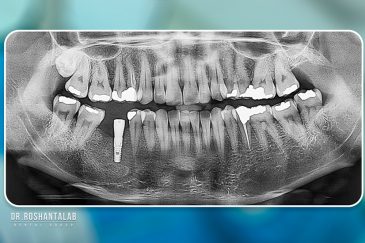

انتخاب بهترین متخصص ایمپلنت که به تکنیکهای روز دنیا مسلط باشد، تضمینکننده سلامت فک و زیبایی لبخند شماست. در کلینیک دندانپزشکی دکتر روشنطلب، ما با بهرهگیری از تجهیزات دیجیتال در ۵ شعبه فعال (تهران، اصفهان، رشت و استانبول ترکیه)، خدمات تخصصی کاشت ایمپلنت دندان را برای بیمارانی که کیفیت و دقت برایشان اولویت دارد، ارائه میدهیم. در این متد، پروسه درمان با ظرافت بالا انجام شده؛ راهکاری ایدهآل برای کسانی که به دنبال درمان بدون درد با بالاترین نرخ موفقیت هستند.

کلینیک تخصصی دندانپزشکی دکتر روشن طلب یکی از پیشروترین مراکز ارائهدهنده خدمات دندانپزشکی در منطقه است که با پنج شعبه فعال در تهران، رشت، اصفهان و استانبول ترکیه، خدمات با کیفیتی را به بیماران داخلی و بینالمللی ارائه میدهد. این کلینیک به دلیل تخصص و تعهد به ارائه خدمات با کیفیت در محیطی آرام و حرفهای، شهرت جهانی کسب کرده است. با تیمی متشکل از جراحان مجرب و استفاده از تجهیزات پیشرفته و برندهای معتبر، تضمینکننده نتایج ماندگار و رضایتبخش است.

هزینه شفاف، همراه با پشتیبانی کامل بیماران بینالمللی، این کلینیک را به گزینهای ایدهآل برای کسانی تبدیل کرده است که به دنبال درمانهای دندانپزشکی با کیفیت در ایران یا ترکیه هستند. چه در تهران، رشت، اصفهان یا استانبول، کلینیک دکتر روشن طلب با تمرکز بر راحتی بیمار و استفاده از فناوریهای مدرن، لبخندی زیبا و سالم را به شما هدیه میدهد.